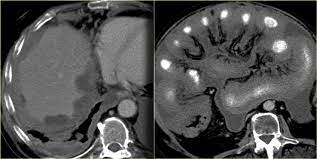

Malignant Mesothelioma Imaging Practice Essentials Radiography Computed Tomography from img.medscapestatic.com In this review we present the key findings in the most common interstitial lung diseases. The mesothelioma specialty care center at upmc hillman cancer center provides a comprehensive treatment approach to this challenging disease. Am j respir crit care med 2010; Factors predictive of survival among 337 patients with mesothelioma treated between 1984 and 1994 by the cancer and leukemia group b. This is why life expectancy often depends on whether a person is treated at a specialized cancer center where they have access to the best mesothelioma doctors. The center brings together experts in thoracic surgical oncology, pulmonology, pathology, radiology, pain management, and medical and radiation oncology. Hales has worked to integrate the efforts of specialists in medical oncology, thoracic surgery, interventional pulmonology, pathology and radiology. Support for patients and families.

A history of asbestos exposure or pulmonary asbestosis should alert the radiologist to the possibility of an existing or developing pleural mesothelioma. Foster, mihir patel, betty l. Searches related to mesothelioma cxr pictures of lungs with mesothelioma mesothelioma images mesothelioma radiology assistant mesothelioma symptoms mesothelioma diagnosis We understand that this is a very stressful time. Saeed, ammar alkhazna, tim quinn, kara m. The fellowship is composed of rotations. A phase ii study led by researchers from the university of texas md anderson cancer center found that. Dust deposition and lymphatic clearance: Am j respir crit care med 2010; Malignant mesothelioma of the pleura. He is currently assistant professor of radiology at the university of michigan medical As a doximity member you'll join over a million verified healthcare professionals in a private, secure network. mesothelioma, minimally invasive surgery, photodynamic therapy, malignant pleural.